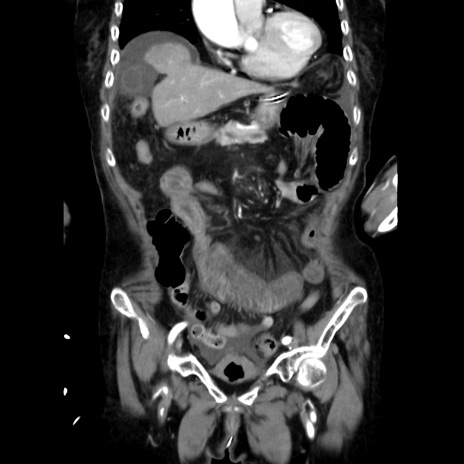

症例40(冠状断像)

【症例】90歳代女性

【主訴】腹痛・嘔吐

【現病歴】 食欲低下、嘔吐があり昨日他院受診。肺炎と診断され入院となる。入院後より腹部全体に圧痛あり。胃管留置され経過みていたが、症状持続するため、

当院転院となる。

【既往歴】胸椎圧迫骨折、胆石症

【身体所見】腹部:中央に激痛あり、圧痛あり、反跳痛不明

【データ】WBC 17100、CRP 18.82

冠状断像